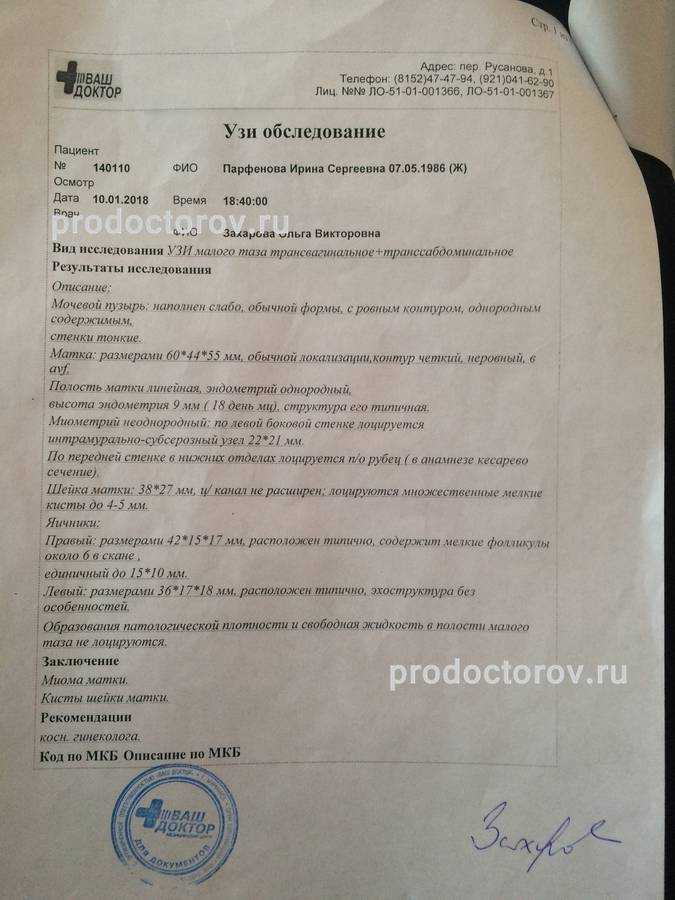

УЗИ малого таза

УЗИ органов малого таза в норме

УЗИ органов малого таза: положения матки

УЗИ ОМТ матка, маточнае трубы, яичники

Почему разные заключения на УЗИ?